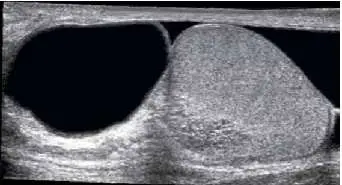

68.附圖為陰囊超音波影像,其最可能的診斷為下列何者?

- 提供的影像為陰囊的二維灰階超音波(2D grayscale ultrasound)。

- 右側構造:可見一呈現橢圓形、內部回音(echogenicity)均勻的中等回音實質構造,此為正常外觀的睪丸(testis)。

- 左側與周邊構造:在睪丸的旁邊與外圍,存在一個巨大、界線清楚且完全「無回音」(anechoic,在影像上呈現全黑)的區域。

- 聲學特徵:此無回音區的後方可觀察到「後方回音增強」(posterior acoustic enhancement),這是典型液體(cystic/fluid)成分的超音波物理特性。

- 液體性質:此無回音區內部清澈,沒有明顯的內部回音(internal echoes)、分隔(septations)或漂浮物,代表這是一大包單純的漿液性液體(simple fluid),蓄積在睪丸鞘膜(tunica vaginalis)的臟層與壁層之間。